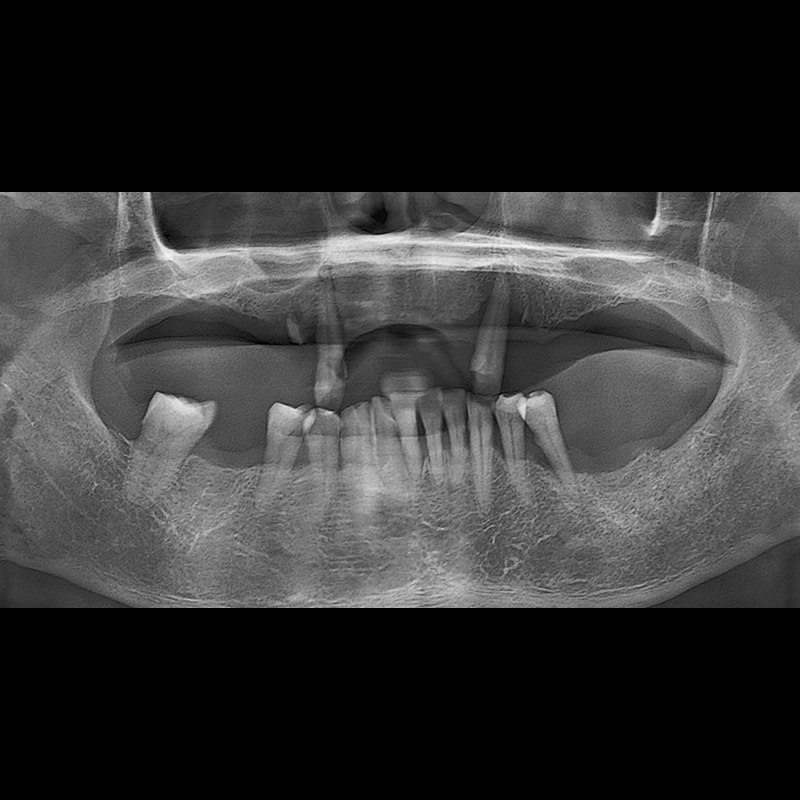

种植牙前后的照片 2025.05.30

在缺失的牙齿部分和难以挽救的牙齿位置植入了种植牙。